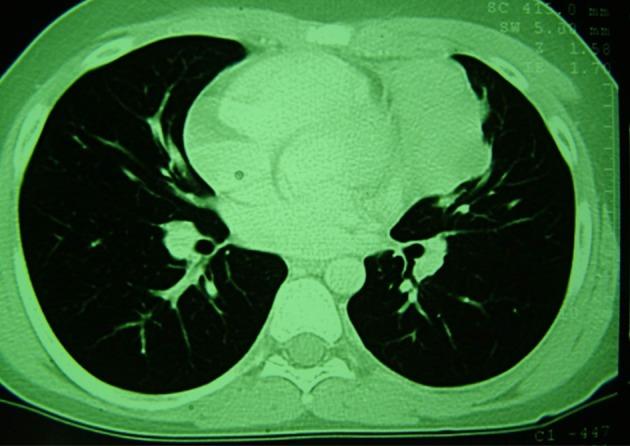

A 15-year-old boy has presented with a mass that located near by the heart in the left side of mediastinum with invasion to anterior mediastinum from two years ago. In biopsy, nasopharyngeal carcinoma, non-keratinizing type, has diagnosed while there was no involvement of nasopharyngeal region. Patient has treated by 70 Gy (2.0 Gy/fraction) radiotherapy plus concomitant chemotherapy with base of docetaxel. But the mass had no regression. Then, the patient has treated with Cisplatin 100 mg/m IV on days 1, 22, and 43 with radiation, then cisplatin 80 mg/m IV on day 1 plus fluorouracil (5-FU) 1000 mg/m/day by continuous IV infusion on days 1 - 4 every 4wk for 3 cycles and after remission interferon beta has added to treatment for 6 months duration as a maintenance therapy. After 1 year follow up; the patient was in complete remission. In the course of therapy, only hypothyroidism has occurred.